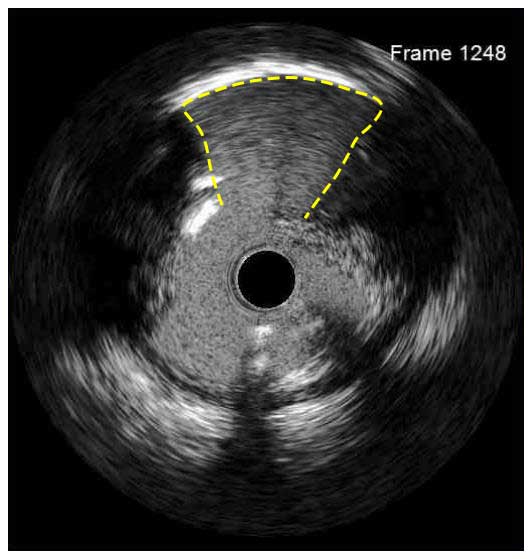

Following stent underexpansion, edge dissection after stent implantation is the second most important predictor of future adverse events. Dissections are classified by IVUS as intimal (limited to intima), medial (extending into the media), adventitial (propagating through EEM), intramural hematoma with blood accumulation within the media, and intra-stent separation of neointimal hyperplasia from stent struts.¹

While minor intimal dissections are unlikely to be clinically significant and do not require any additional treatment, extensive dissections disrupting the medial layer should be treated with additional stent implantation. Lateral extension >60°, longitudinal length >2 mm and involvement of medial or adventitial layers, especially at the distal stent edge, characterize the clinically significant dissections requiring correction.² Intramural hematomas represent another stent edge-related issue, which can increase the risk of future events. It might appear as edge stenosis on angiography, and the progression of uncovered hematoma may lead to early stent thrombosis.